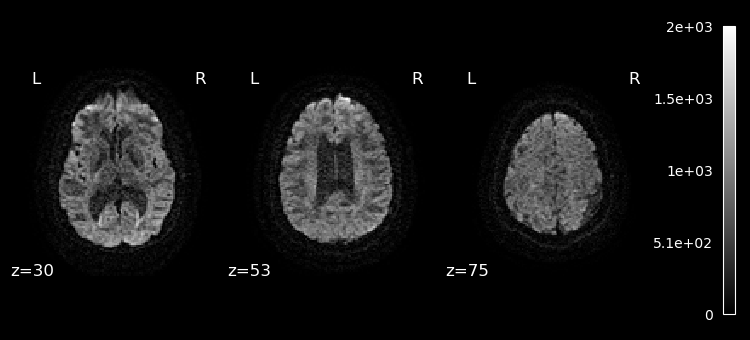

Lets plot the first 10 volumes.

%matplotlib inline

from nilearn import image

from nilearn.plotting import plot_epi

selected_volumes = image.index_img(dwi, slice(0, 10))

for img in image.iter_img(selected_volumes):

plot_epi(img, display_mode="z", cut_coords=(30, 53, 75), cmap="gray")